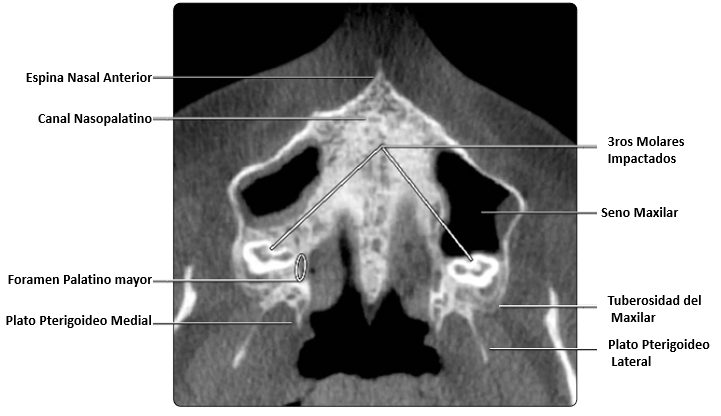

En esta imagen se muestra una vista axial con terceros molares impactados, es importante localizar estructuras anatómicas adyacentes y tomar nota de la proximidad que tienen estos a otros dientes si la extracción está planificada.